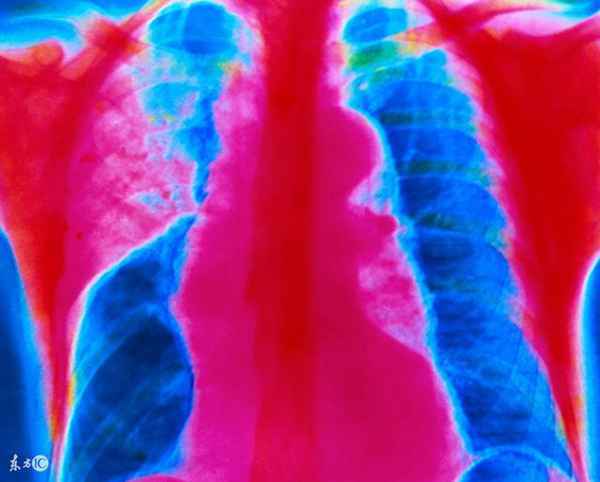

1、病变从上呼吸道开始,有充血、单核细胞浸润,向支气管和肺蔓延,呈间质性肺炎或斑片融合性支气管肺炎。一般起病缓渐,有乏力、咽痛、咳嗽、发热、纳差、肌痛等。半数病例无症状。X线显示肺部多种形态的浸润影,呈节段性分布,以肺下野为多见,有的从肺门附近向外伸展。支气体肺炎可在3-4周自行消散。儿童可并发鼓膜炎和中耳炎,伴有血液(急性溶血、血小板减少性紫癜)或神经(周围性神经炎、胸膜炎等)等并发症或雷诺现象(受冷时四肢间歇苍白或紫绀并感疼痛)时,则病程延长。